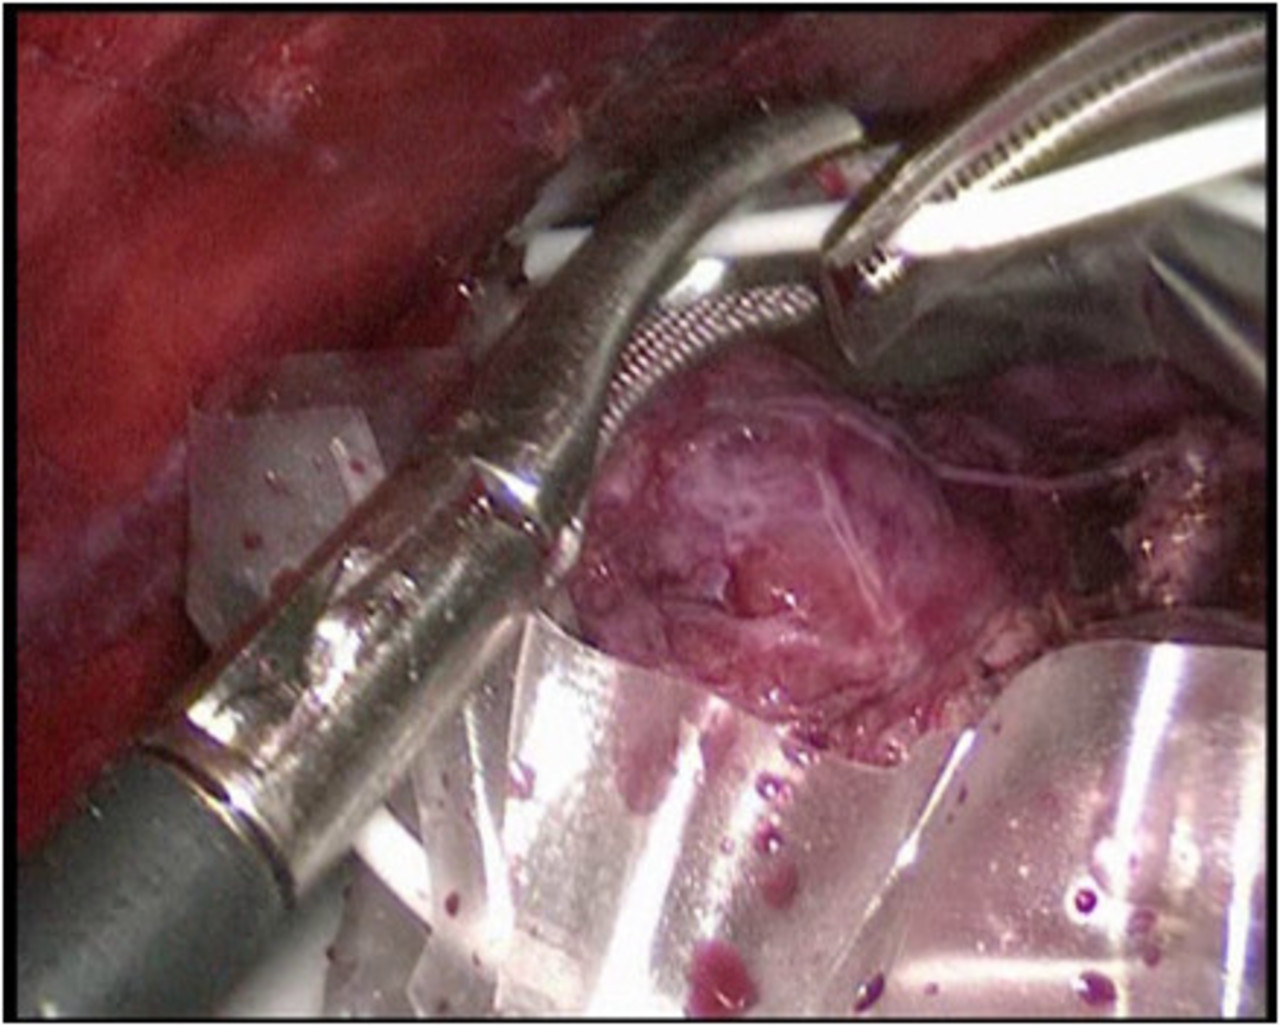

Wir führen neben der konventionellen Schnittoperation seit Jahren auch als eine der wenigen Kliniken in Deutschland die minimal invasive Schilddrüsenresektion nach der „ABBA-Methode“ durch. Welche Operationsmethode im Einzelfalle eingesetzt werden kann hängt von der Schilddrüsenerkrankung und der Größe ab und wird im Vorfeld mit dem Patienten ausführlich abgewogen und besprochen.

Minimal invasive Schilddrüsenoperation (ABBA):

Bei der von uns durchgeführten minimal invasiven Schilddrüsenoperationstechnik handelt es sich um die sog. „ABBA-Technik“ (Axillo-bilateral-breast-approach). Dabei wird die Schilddrüse durch einen ca. 2 cm langen Hautschnitt im Bereich der vorderen Achselhöhle sowie über 2 winzige Schnitte im Bereich der Brust (Randbereich der Brustwarze) operiert. Bei dieser Technik erfolgt die Präparation streng im Unterhautfettgewebe – Nerven, Gefäße oder die Brustdrüse werden dabei nicht tangiert. Ähnlich wie bei minimal invasiven Bauchoperationen wird das Operationsgebiet mit CO2-Gas gefüllt, um ausreichend Raum für die Einführung der feinen Operationsinstrumente zu erreichen. Die Schilddrüse wird dann unter Kamerasicht analog der herkömmlichen Operationstechnik operiert. Die Übersicht bei dieser Operation ist hervorragend; sämtliche Nerven- und Gefäßstrukturen können genau identifiziert werden. Ebenso werden die Stimmbandnerven mittels Neuromonitoring kontrolliert und die Nebenschilddrüsenkörperchen dargestellt und geschont.